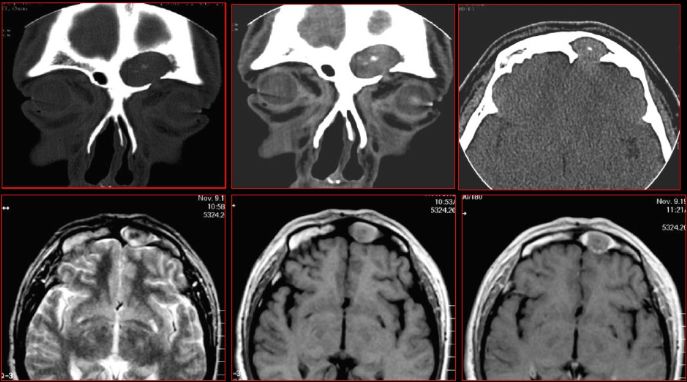

鼻窦炎—骨质改变

鼻窦炎—骨质增生

鼻窦炎—骨质增生及脑膜炎